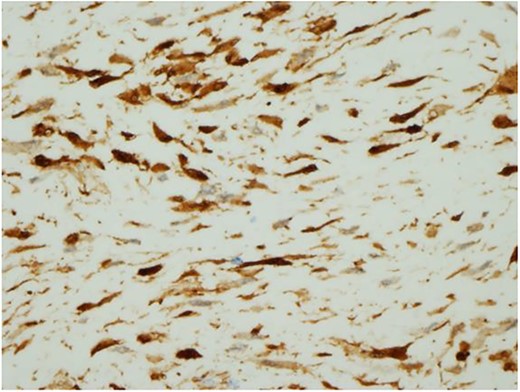

Ultrasound guided biopsy was performed, which showed spindle cells fascicles with collagen formation. The cells were stained positive to beta-catenin nuclear staining, and negative for SMA, CD34, Desmin and S100 (Figs 3 and 4). The diagnosis of desmoid fibromatosis was confirmed.

Histopathological findings. Spindle cells fascicles with collagen formation (H&E ×100).